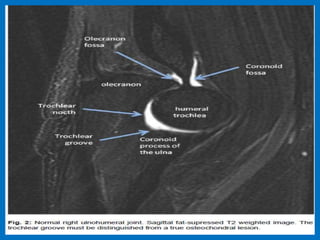

MR anatomy of the elbow joint.

UCL (black arrows) and overlying common flexor tendon (black arrowhead) on the medial side (MED).

On the lateral side (LAT ) is the radial collateral ligament with an adjacent synovial fold (white arrow),

the annular ligament (white arrowhead ), and the overlying extensor carpi radialis brevis origin (open

arrow). (b) Coronal T2-weighted FS MR image through the elbow demonstrates the posterior band of

the UCL (black arrow) on the medial side and LUCL (white arrows) on the lateral side.